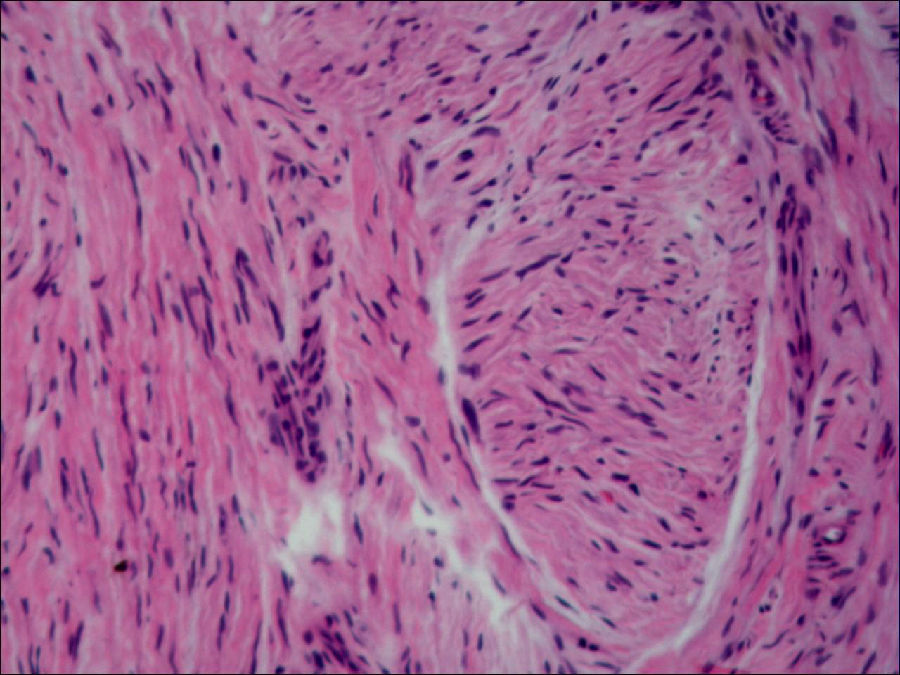

佚名 前已述及,肺除有气体交换能外,支气管树上皮内还有弥散的神经内分泌细胞。近些年的研究还发现肺内进行着诸多物质代谢和转化作用,尤其表现在肺血管内皮细胞。全身血液均通过肺循环血管,故肺血管内皮细胞的代谢作用对机体的影响很大。内皮细胞游离面有血管紧张素转换酶,可将血液中血管紧张素Ⅰ转化为血管紧张素Ⅱ,后者的缩血管作用较前者强50倍。肺循环血内的血管